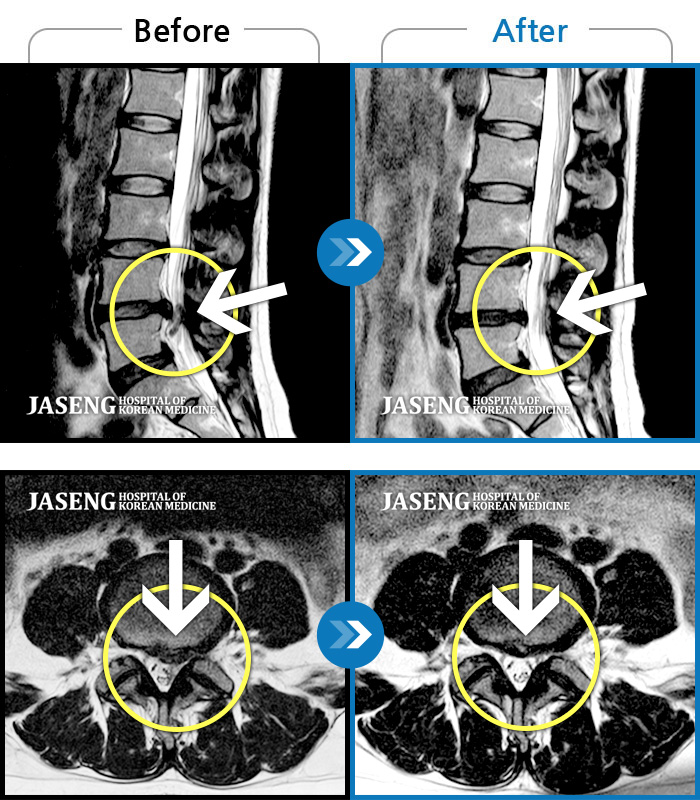

허리디스크

천안 · 김세정 원장

요통 및 다리통증이 매우 심해 움직이기 어려운 상태였습니다.

촬영시기

2023.03.20 ~ 2023.12.26